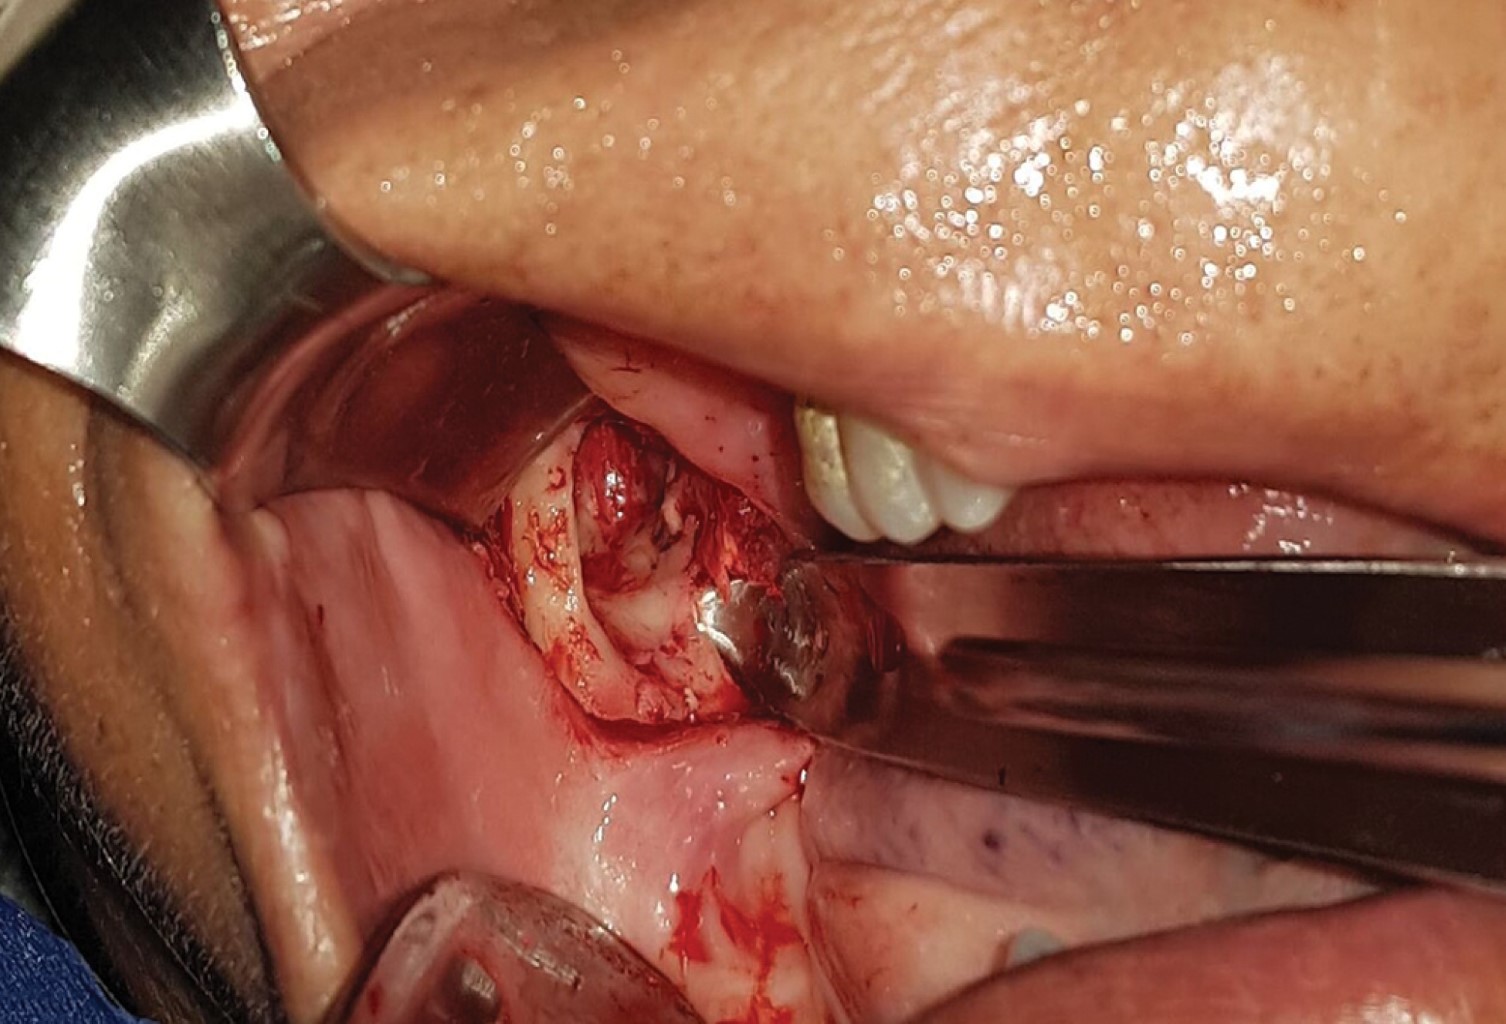

Heterotopic third molars are teeth that are embedded in the maxilla and mandible, remote from their usual eruption site. Its etiology is not well defined and there are various theories at the moment. These teeth can appear in different areas of the bone's structures, having a predilection for the jaw. They usually appear between the second and seventh decade of life, and in most cases are imaging findings. The mandibular third molar is the tooth with the most frequent heterotopia, being its usual location in the mandibular branch and in the subcondylar region. The dentigerous cyst is the most common associated pathology. We present a case of a long evolution heterotopic third molar in the right mandibular branch, related to a dentigerous cyst which was managed under local anesthesia. The etiology, surgical technique and special considerations related to heterotopic teeth are described.

Figure 2